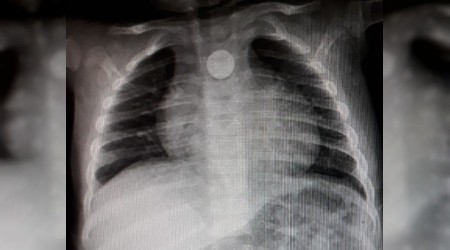

Evinde oynarken yerde bulduğu madeni 1 lirayı yutan 9 aylık bebek ölümden döndü. Röntgen filminde bebeğin boğazındaki 1 lirayı farkeden doktorlar operasyonla parayı çıkardı. Evine dönen Mustafa ise her şeyden habersiz oyunlarına devam etti

9 aylık Mustafa bebek yuttuğu 1 lira yüzünden az kalsın ölüyordu. Olay geçtiğimiz gün Bursa İnegöl'de yaşandı. Abir ve İbrahim Osman çiftinin tek çocuğu olan 9 aylık Mustafa Osman, evde oyun oynadığı sırada yerde bulduğu 1 lirayı yuttu.

Boğazına takılan madeni para yüzünden nefessiz kalan minik bebek önce İnegöl Devlet Hastanesi'ne ardından da Bursa Şevket yılmaz Eğitim Araştırma Hastanesine götürüldü.

Yoğun bakıma alınan minik bebeğe önce film çekildi. 9 aylık Mustafa'nın boğazına takılan madeni para filmde ortaya çıkınca doktorlar tarafından operasyon yapıldı. Boğazındaki 1 lira çıkarılan minik bebek daha sonra rahat nefes almaya başladı.

1 gün hastanede müşahade altında tutulan küçük çocuk bugün taburcu edildi. Doktorların zamanında müdahalesiyle yeniden hayata dönen küçük çocuğu evinde yeniden oyuncaklarıyla oynamaya başlaması ev sakinlerini sevindirdi.

Mustafa'nın amcası Hüseyin Osman, "Yeğenim oyun oynarken yerde 1 lira görüyor ve yutmaya çalıştığı sırada boğazına takılı kalıyor. Bizde hemen hastane götürdük. Daha sonra bizi Bursa'ya gönderdiler. Çok şükür Bursa'daki hastanede operasyonla para çıkartıldı. Allah'a şükürler olsun ki yeğenimize bir şey olmadı" dedi.